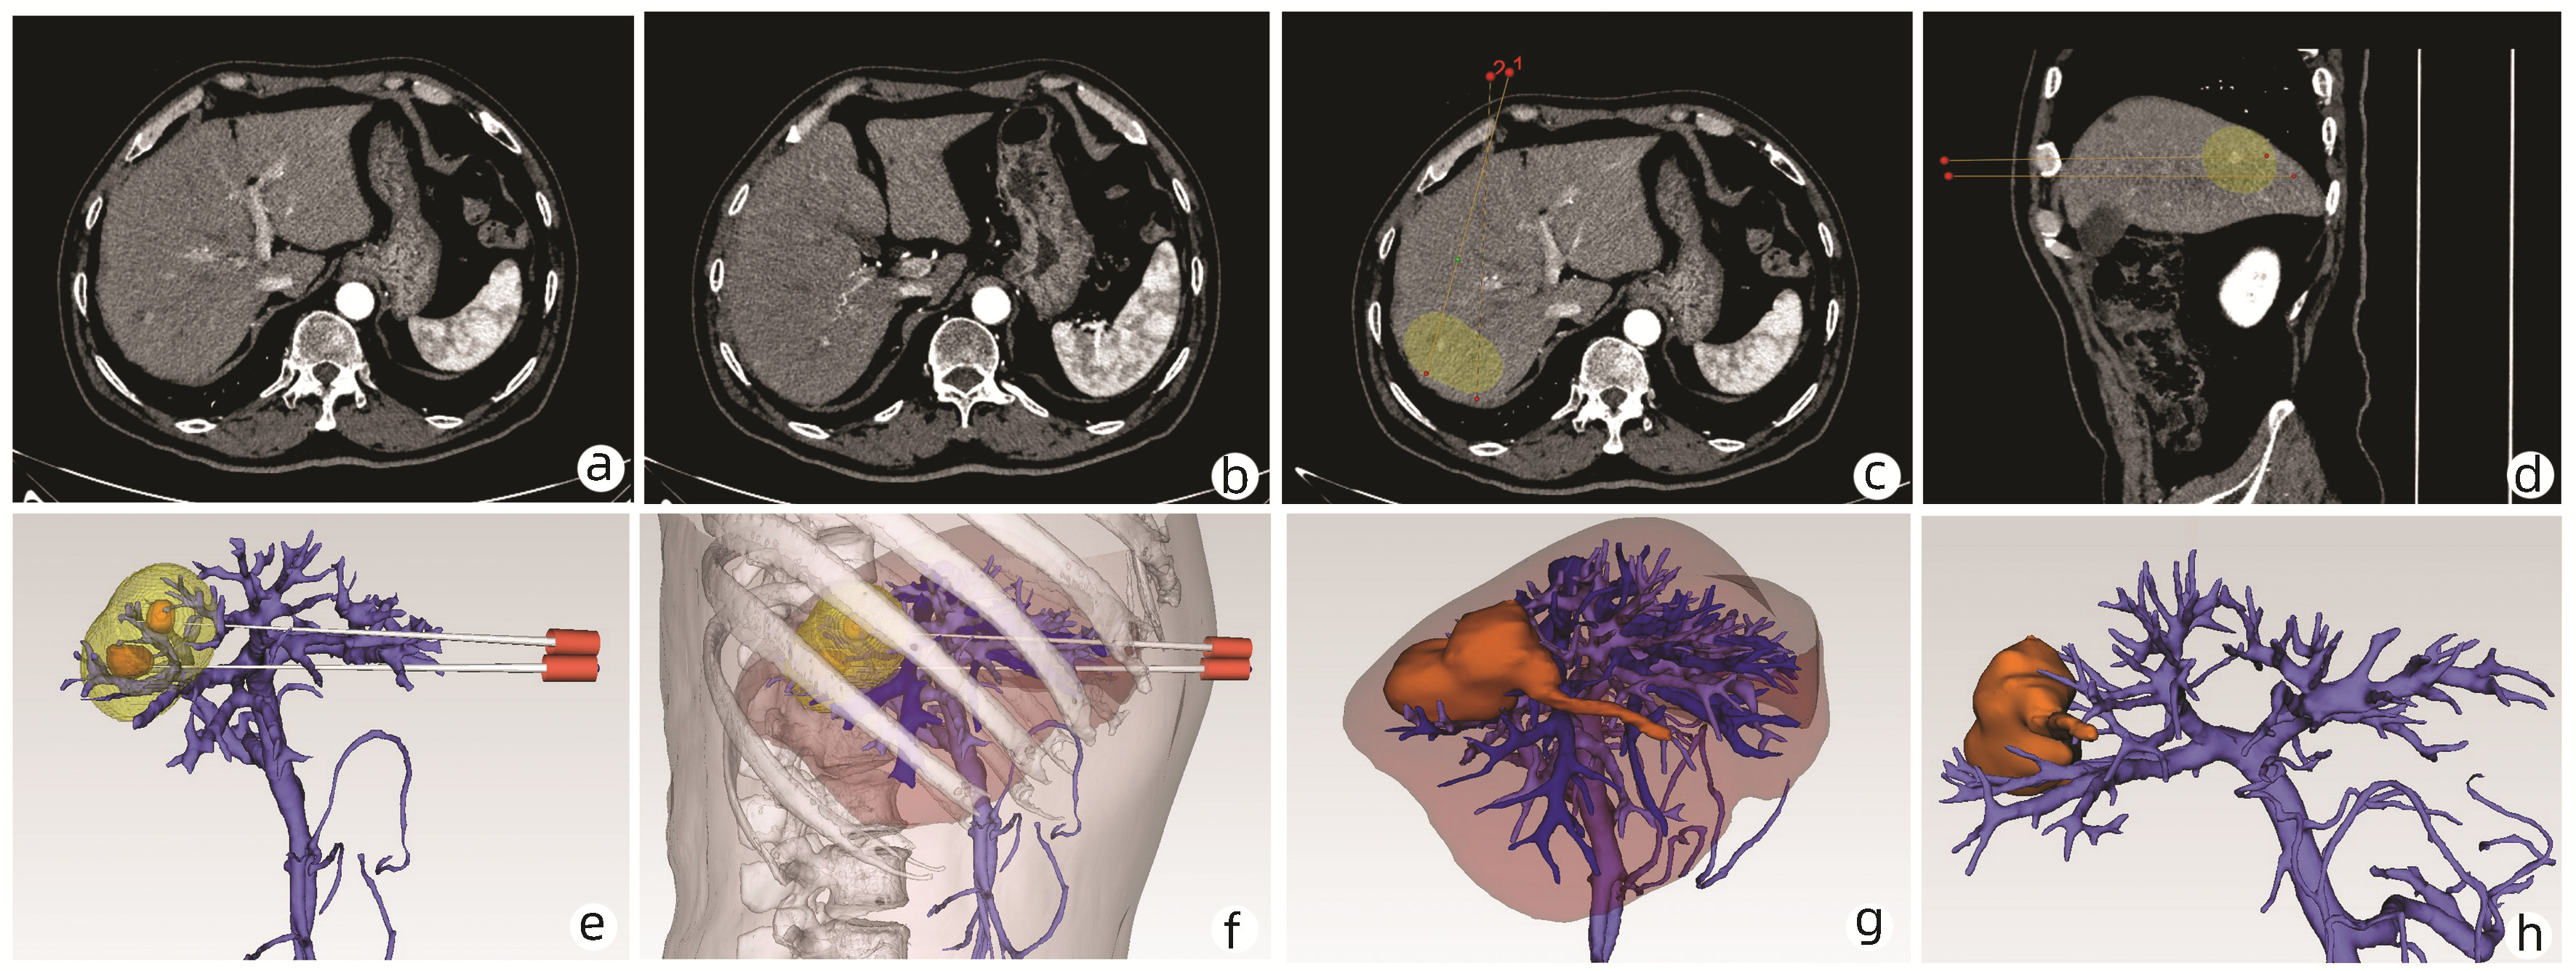

Application of the three-dimensional visualization ablation planning system in radiofrequency ablation for hepatocellular carcinoma

Rong HE, Zhe JIA, Li JIANG, Ke ZHANG

2022, 38(9): 2046-2052. DOI: 10.3969/j.issn.1001-5256.2022.09.019

Abstract(1069) HTML (779) PDF (4804KB)(176)

Abstract:

Objective  To investigate the significance of the three-dimensional visualization ablation planning system in radiofrequency ablation for liver cancer.  Methods  A total of 71 patients who received radiofrequency ablation for hepatocellular carcinoma in Beijing Ditan Hospital, Capital Medical University from July 2017 to December 2020 were enrolled as subjects. The 34 patients in the three-dimensional group used the three-dimensional visualization ablation planning system for radiofrequency protocol planning before surgery and the 37 patients in the two-dimensional group used the two-dimensional image for radiofrequency protocol planning before surgery. The two groups were compared in terms of the indices such as the first-attempt success rate of puncture, complete tumor ablation rate, and tumor-free survival. The Fisher's exact test, the chi-square test of continuous correction, or the Pearson chi-square test was used for comparison of categorical data between two groups; the t-test was used for comparison of normally distributed continuous data between groups, and the Mann-Whitney U test was used for comparison of non-normally distributed continuous data between groups. The Kaplan-Meier method was used to plot survival curves, and the Log-rank (Mantel-Cox) test was used for comparison of tumor recurrence and survival; the Cox proportional-hazards regression model analysis was used to investigate the influencing factors for tumor-free survival.  Results  Compared with the two-dimensional group, the three-dimensional group had a significantly higher first-attempt success rate of puncture (94.12% vs 75.68%, Pearson χ2=4.183, P=0.041) and a significantly shorter median time of puncture (5 minutes vs 7 minutes, Z=-2.407, P=0.013). There was no significant difference in complete ablation rate between the three-dimensional group and the two-dimensional group (97.06% vs 91.89%, continuous correction χ2=0.183, P=0.669). There were significant differences in the 1-, 2-, and 4-year cumulative tumor-free survival rates between the three-dimensional group and the two-dimensional group (90.8%/78.8%/72.8% vs 61.5%/55.9%/44.7%, χ2=5.073, P=0.024). The multivariate Cox regression analysis showed that preoperative planning method, complete or incomplete ablation, and alpha-fetoprotein at 1 month after surgery were independent influencing factors for the tumor-free survival of patients with liver cancer after radiofrequency ablation (all P < 0.05).  Conclusion  Radiofrequency ablation planning via the three-dimensional visualization ablation planning system can ensure the therapeutic effect of radiofrequency ablation, reduce the recurrence rate of liver cancer, and prolong the tumor-free survival of patients.